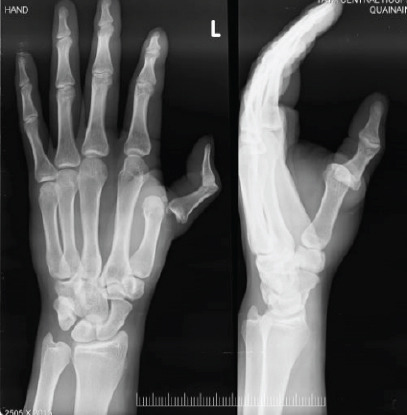

Introduction: Metacarpophalangeal (MCP) joint dislocation and its pathoanatomy was first discussed in detail in an article written by Kaplan et al . ,in 1957. They had identified certain features of complex, that is irreducible MCP joint dislocation through closed method to differentiate from a simple MCP joint dislocation, that is MCP joint dislocation that can be reduced by closed method. The complex MCP joint dislocations (mostly involving the index finger) are called Kaplan dislocations.Here, we describe two cases of MCP joint dislocations to highlight the differences between complex and simple MCP joint dislocation in their clinical appearances, X-rays, and management protocol.

Case report: In the first case, the injured patient was a 17-year-old young cricketer, who sustained the injury while playing the game. After careful clinical examination and studying the X-rays, we assured the patient and treated his injury by closed reduction method. After undergoing the post-reduction splinting and physiotherapy, the patient has recovered completely and he is back to playing cricket.In the second case, the patient was an elderly lady; she got her left index finger dislocated while trying to forcefully hold a moving object. After careful clinical examination and studying the X-rays, we counselled her and treated her injury through open reduction method. After following the post-operative splinting and physiotherapy, the patient is doing well but her index finger extension is restricted in the terminal ranges.